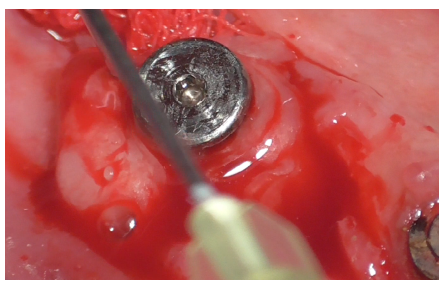

The Ultrasonic Device was equipped with the ES004E insert (patented by Esacrom, Dr. Tarquini), creating an ultrasonic bath (Figure 23).

Figure 23

Initially, this insert was used with physiological saline flow (Figure 24) for approximately 1 minute. Subsequently, Ambramicin was applied to the site (Figure 25), capsules were specially opened to use the powdered antibiotic inside, activated for 1 minute using the same bell-shaped insert with physiological saline flow (Figure 26).

Figure 24